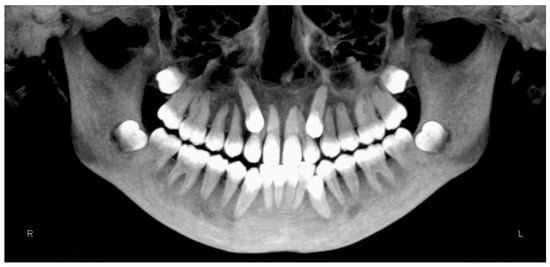

- Evaluation of impacted teeth, a common indication of CBCT in orthodontics. The advantages of CBCT include assessment of the tooth location and position, the stage of development, and status of adjacent teeth. CBCT is justified in these cases, because CBCT has the capability of evaluating the impacted teeth and adjacent structures more accurately than 2D conventional imaging. The benefit–risk ratio is favorable, especially if the CBCT volume is collimated to the impacted tooth. Figure 1, Figure 2, Figure 3 and Figure 4 show an example of impacted maxillary canines, and their proximity to the maxillary lateral incisors. Figure 1 shows an intraoral photograph. The benefit of CBCT acquisition in this case includes the ability to visualize the canines and the lateral incisors in three dimensions, which can be visualized in Figure 2 and Figure 3. In this case, the maxillary right lateral incisor exhibited external root resorption, a finding that would be difficult to see on a conventional 2D panoramic radiograph. Figure 4 shows a Maximum Intensity Projection of a panoramic view derived from the CBCT volume. This unique view is free of magnification, distortion, ghost images, and overlaps frequently seen in conventional 2D panoramic radiography.